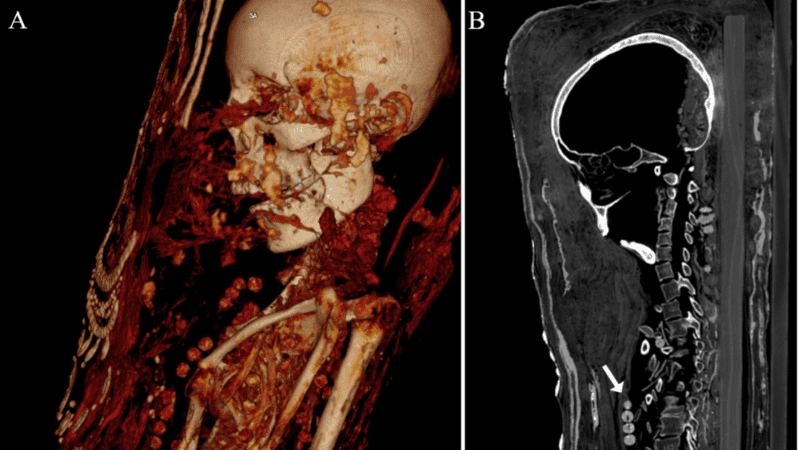

Un equipo de arqueólogos analizó los restos de tres momias egipcias correspondientes al periodo romano tardío —entre finales del siglo III y del siglo IV d.C.—, y descubrió que al menos una de ellas aún conserva el cerebro y otros órganos internos. Estos hallazgos, que aparecen recogidos en la revista Plos One, fueron posibles gracias al uso de nuevos escáneres especializados.

Las momias, que se corresponden con un hombre adulto, una mujer de mediana edad y otra mujer joven, son las únicas cubiertas de estuco que se han encontrado en la antigua necrópolis de Saqqara. En el proceso, los cuerpos se colocaban sobre tablas de madera antes de se envueltos en tela, yeso y oro, añadiéndose en la superficie un retrato de cuerpo entero.

Además, los expertos identificaron cuentas de collares, una horquilla y objetos de metal denso, como sellos de plomo, clavos y dos monedas o medallones, con los que fueron enterrados los individuos.

Finalmente, los resultados del estudio también revelaron otros datos relacionados con la salud de las tres momias, como la presencia de caries, protuberancias entre las vértebras (nódulos de Schmorl) y evidencia de artritis, según publicó RT.